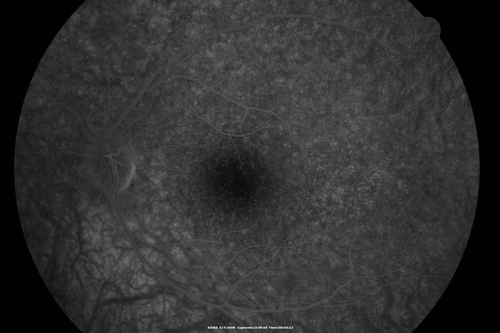

Cuticular Drusen - 26 year old female - Glomerulonephritis

VA 20/25 OU. Images are over 4 years - FA shows starry sky early images - This is because of loss of RPE over the drusen creating very small window defects.

Cuticular Drusen 26 year old woman with history of Glomerulonephritis